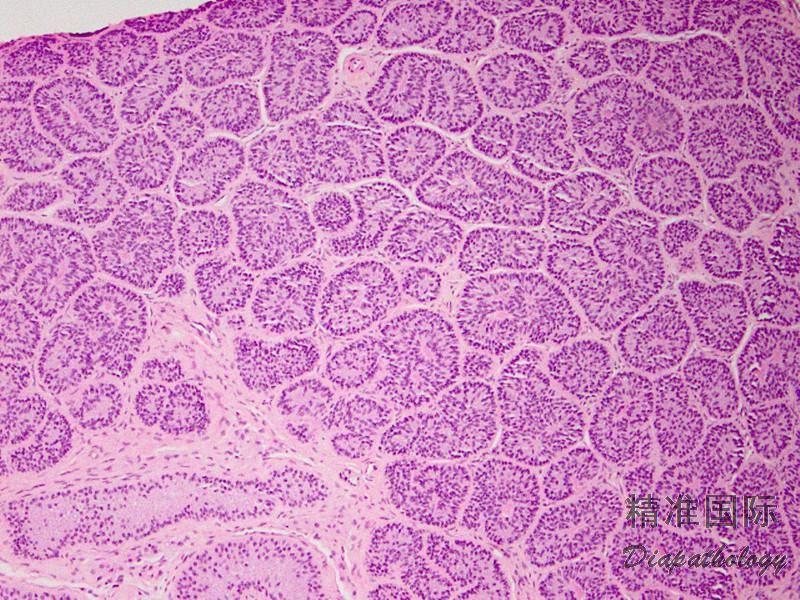

低倍镜下观察,多数病例见管状结构呈结节状分布,间质稀少,少数病例间质丰富;

肿瘤细胞排列成小管,这些管状结构可以呈实性或中央有孔,也可见网状和小管-腺腔结构、索状、束状及单个细胞分布,弥漫性分布少见;小管周围包绕基底膜;

肿瘤细胞胞质中等量,淡染或嗜酸性,偶尔富含脂质或见脂质空泡;细胞核圆形、椭圆或长形,核仁不突出,核沟和核内包涵体不常见;